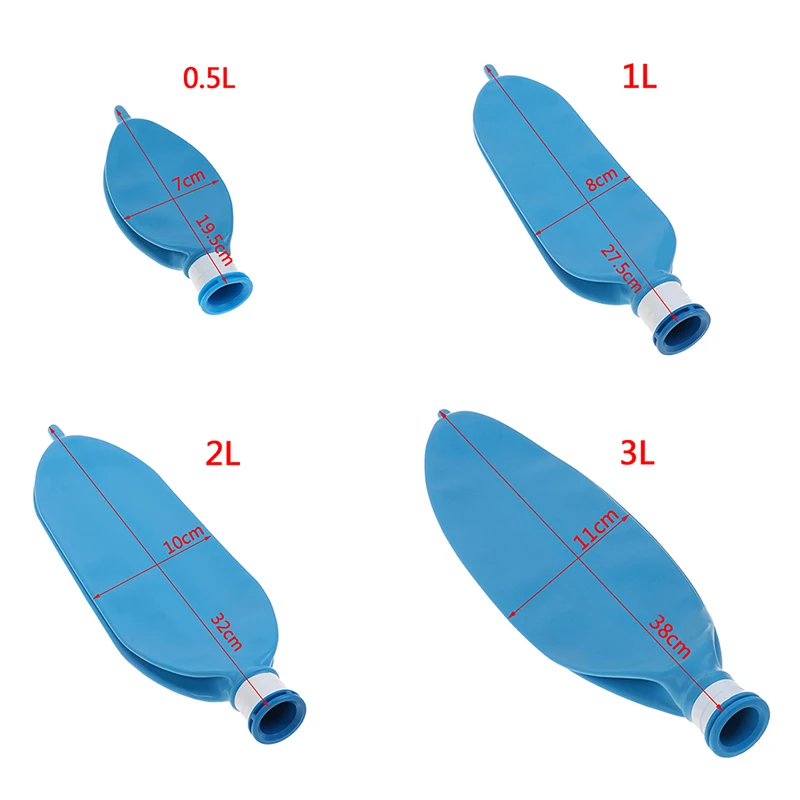

Латексный одноразовый дыхательный аппарат для анестезии объемом л, 1 л, 2 л, 3 л

Описание:Материал: латексРазмер: 0.5л 1Л 2л 3лЦвет: синий

Примечания:Из-за разницы между различными мониторами изображения могут не отражать фактический цвет изделия.Сравните размеры деталей с вашими, пожалуйста, учитывайте погрешность в 1-3 см из-за ручного измерения.